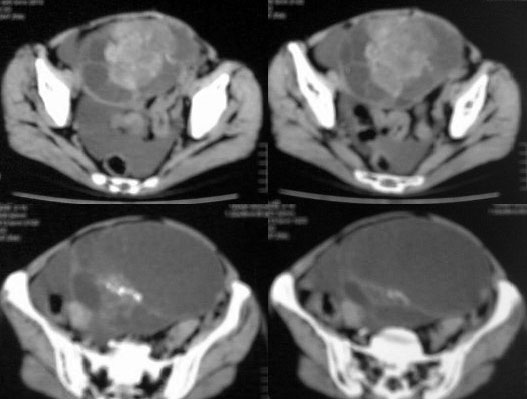

患者女性,45岁,因下腹疼痛,包块就诊,月经不太规则,其他未能提供有价值病史,请讨论

对不起各位,第一次试传,经验不足,补充一下资料,患者女性,45岁,因下腹疼痛,包块就诊,月经不太规则,其他未能提供有价值病史

ct图像有点不连续,且大部画面模糊,有增强吗?就此而论我看向源于卵巢的,首先考虑囊腺ca或瘤.

此患者手术病理结果已出:卵巢囊腺瘤。